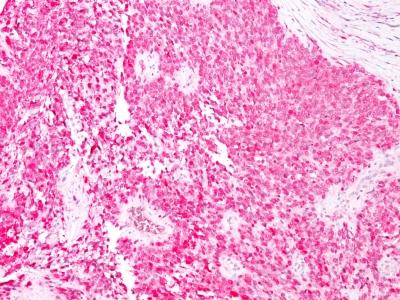

Formalin--paraffin human Melanoma stained with S100A1 Monoclonal Antibody (4C4.9) (AEC Chromogen)

S100 belongs to the family of calcium binding proteins. S100A and S100B proteins are two members of the S100 family. S100A is composed of an alpha and beta chain whereas S100B is composed of two beta chains. S-100 protein has been found in normal melanocytes, Langerhans cells, histiocytes, chondrocytes, lipocytes, skeletal and cardiac muscle, Schwann cells, epithelial and myoepithelial cells of the breast, salivary and sweat glands, as well as in glial cells. Neoplasms derived from these cells also express S-100 protein, albeit non-uniformly. A large number of well-differentiated tumors of the salivary gland, adipose and cartilaginous tissue, and Schwann cell-derived tumors express S-100 protein. Almost all malignant melanomas and cases of histiocytosis X are positive for S-100 protein. Despite the fact that S-100 protein is an ubiquitous substance, its demonstration is of great value in the identification of several neoplasms, particularly melanomas and their metastases.